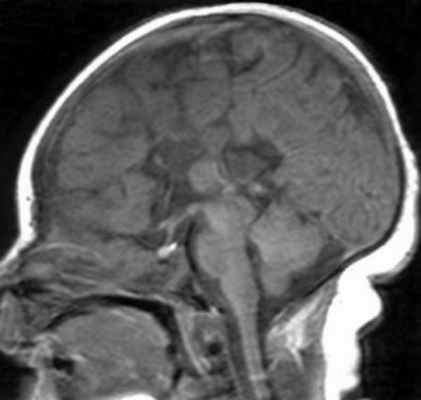

МРТ. Т1-зависмая сагиттальная томограмма. Синдром Экарди.

Кроме того полимикрогирия может входить в состав синдром Экарди (Aicardi) -Х-связанной доминантной патологией. Он протекает в виде спазмов и хориоретинопатии. При МРТ часто выявляются гипоплазия мозжечка, агенезия или недоразвитие мозолистого тела, кисты ЗЧЯ и средней линии, папилломы сосудистого сплетения.

Аномально малое число извилин в связи с неполными бороздами называется пахигирией. Обычно, она также локальная, извилины широкие и сглаженные. Сочетание участков пахигирии и агирии называют лиссэнцефалией I типа. При МРТ определяется утолщение коры, вертикальные Сильвиевы борозды и часто выпрямленные гиппокампы. Клинические проявления укладываются в различные формы (синдромы Миллера – Декера, Нормана – Робертса и т.д.), проявляющиеся в первый год жизни. Тип II отличается нарушением структуры самой коры, которая пронизана сосудами и фиброглиальными пучками. Этот тип сочетается с гидроцефалией и неполной миелинизацией. Характерно клиническое проявление в виде синдрома Уокера – Варбурга.

а - Т1-ВИ, сагиттальная плоскость. Агирия затылочной доли. Извилины теменной доли утолщены, широкие.

б - IR ИП, аксиальная плоскость. Толщина коры увеличена, желудочки мозга расширены.